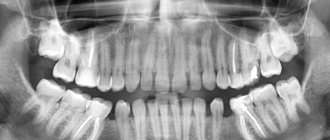

A child’s milk teeth differ from permanent teeth in their structure, shape and color. We strongly recommend that you look at numerous photos in which you can easily tell the difference. In addition, children's teeth have a thin layer of enamel, a small crown and dentin. In the photographs you can easily notice that such teeth have widely spaced roots that are located at an angle. This feature is explained by the need for the formation of permanent teeth.

An X-ray of a child's jaw with baby teeth will help determine how much the new molars have formed. If you pull out children's teeth before the molars are formed, you are likely to encounter serious deficiencies. This usually causes a cosmetic defect in the form of a diastema, or a large gap between the teeth. In addition, it is very important to monitor the condition of baby teeth. If they are not treated promptly for caries and other diseases, there is a high risk of developing serious problems in the future.

X-rays of children's primary teeth are one of the basic diagnostic procedures in pediatric dentistry. This method helps to assess the condition of dental roots, soft tissues near the element of the dentition, and identify the rudiments of molars. Using X-rays, the specialist assesses the condition of the jaw and announces the likely timing of the loss of primary teeth.

• The roots of baby teeth are shorter, widely spaced and angled. This is explained by the need for the formation of molars;

• panoramic image of the jaw - displays a picture of the dentition along with the rudiments of the radical elements;